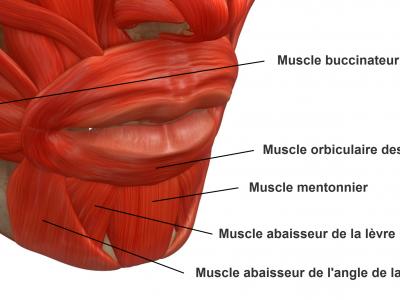

- Un complexe musculaire labio-mentonnier (figure 1) comprenant essentiellement :

-

- Le muscle buccinateur, muscle paire dont la terminaison antérieure au niveau de la commissure labiale permet d’étirer l’orifice buccal

- Le muscle orbiculaire des lèvres, muscle médian s’étendant d’une commissure à l’autre et permettant l’occlusion de la bouche

- Le muscle mentonnier, muscle paire étendu d’une fossette de la symphyse mentonnière à la peau du menton, il permet d’élever les parties molles du menton

- Le ligament mentonnier, médian, interposé entre les deux muscles mentonnier, inséré sur la symphyse mentonnière et la peau de la région mentonnière, il crée la fossette du menton

- Le muscle abaisseur de la lèvre inférieure, muscle paire étendu de la partie antérieure de la ligne oblique de la mandibule à la lèvre inférieure

- Le muscle abaisseur de l’angle de la bouche, muscle paire étendu de la partie antérieure de la ligne oblique de la mandibule à la commissure labiale

Ce complexe musculaire comprend un tonus constant, et une activité en fonction (manducation, déglutition, ventilation, élocution, mimique) qui peut être modifiée par la présence de dysfonctions ou de parafonctions.

Figure 1 : anatomie du complexe musculaire labio-mentonnier